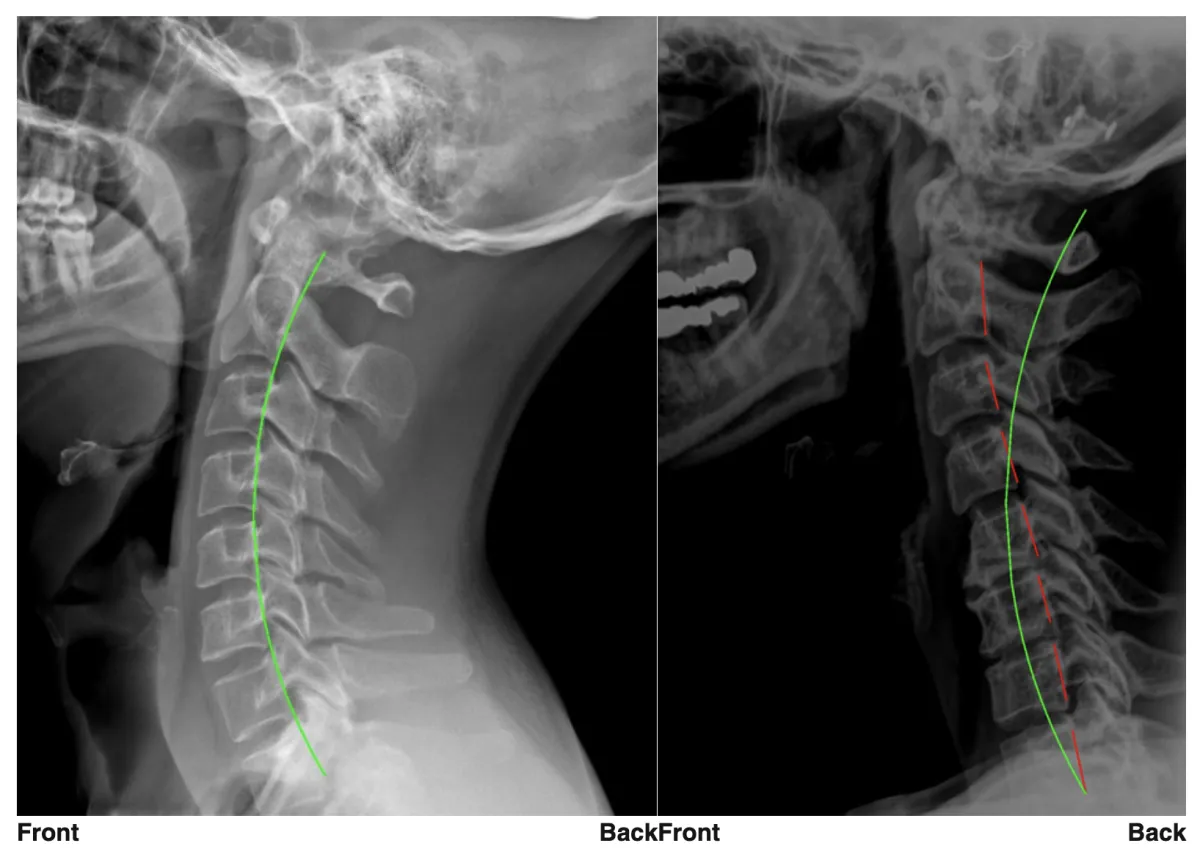

Chiropractic was the first profession to use x-ray to measure spinal alignment, and we use state-of-the-art technology from PostureRay to visualize your Digital X-Rays to see normal alignment vs. abnormal alignment (seen above in the neck), as well as changes to spinal curves and any damage to the spine caused by long-term vertebral subluxation.